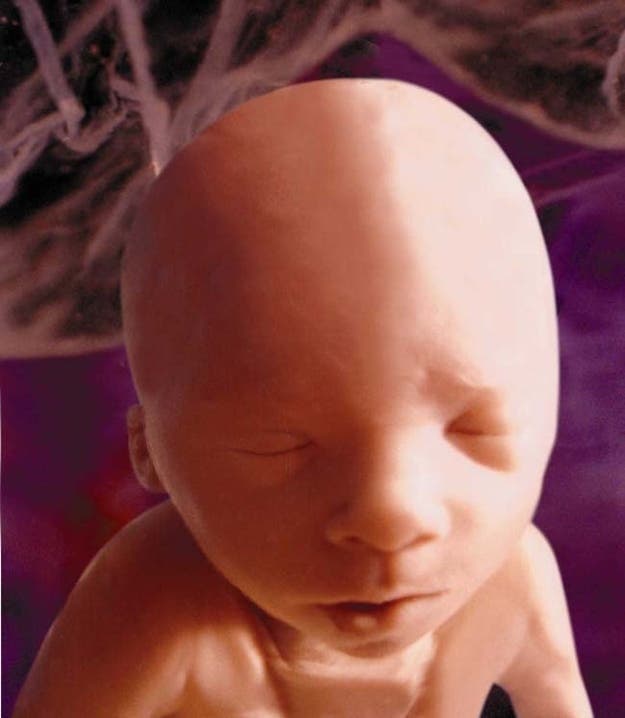

6 – À 16 semaines de grossesse

Cette semaine, bébé passe par un pic de croissance. Il va bientôt commencer à avoir des cheveux et ses ongles de pieds vont également pousser. Ses yeux commencent à bouger sous ses paupières et il prend le cordon ombilical comme jouet, à agripper, tirer puis repousser.